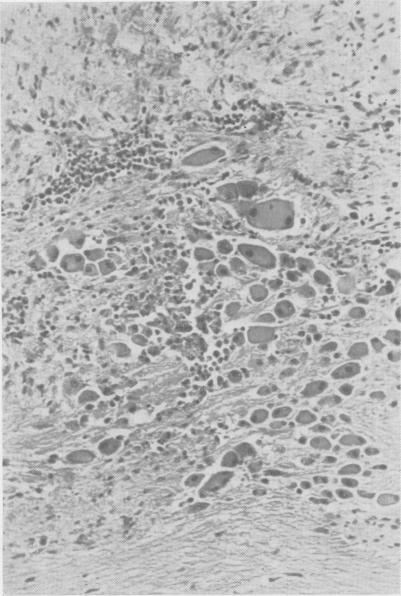

Intrathoracic neurogenic tumors in infants and children; a study of forty cases.

Ann Surg. 1959 Jul;150(1):29-41. doi: 10.1097/00000658-195907000-00003.